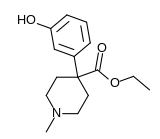

The first fully synthetic opioid was meperidine (later demerol), found serendipitously by German chemist Otto Eisleb (or Eislib) at IG Farben in 1932.[228] Meperidine was the first opiate to have a structure unrelated to morphine, but with opiate-like properties.[199] Its analgesic effects were discovered by Otto Schaumann in 1939.[228] Gustav Ehrhart and Max Bockmühl, also at IG Farben, built on the work of Eisleb and Schaumann. They developed "Hoechst 10820" (later methadone) around 1937.[230] In 1959 the Belgian physician Paul Janssen developed fentanyl, a synthetic drug with 30 to 50 times the potency of heroin.[211][231] Nearly 150 synthetic opioids are now known.[228]